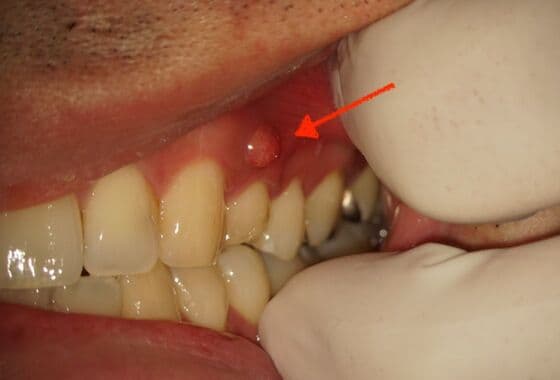

根尖性歯周炎の根尖とは、歯の根の尖端の事を指します。根管内に感染した細菌が原因で根尖のまわりで炎症が起きて根尖に膿がつくられることで様々な歯の不調を引き起こします。これを、「根尖性歯周炎」と言い、根管治療の成功率を大きく下げる病気です。根尖性歯周炎は普段の生活では症状を自覚されないことも多くあります。そのため、痛みが消えたのでそのまま放置してしまい、ある日突然痛みや腫れを感じることも多くあるのです。また、症状が進行すると瘻孔(ろうこう)※右記の写真参照と言われる排膿路(膿の出口)ができることで、痛みを誘発しにくくなります。

瘻孔(ろうこう)

歯ぐきにポツリとできたおできの様なふくらみで根の先端(根尖)に溜まった膿の出口